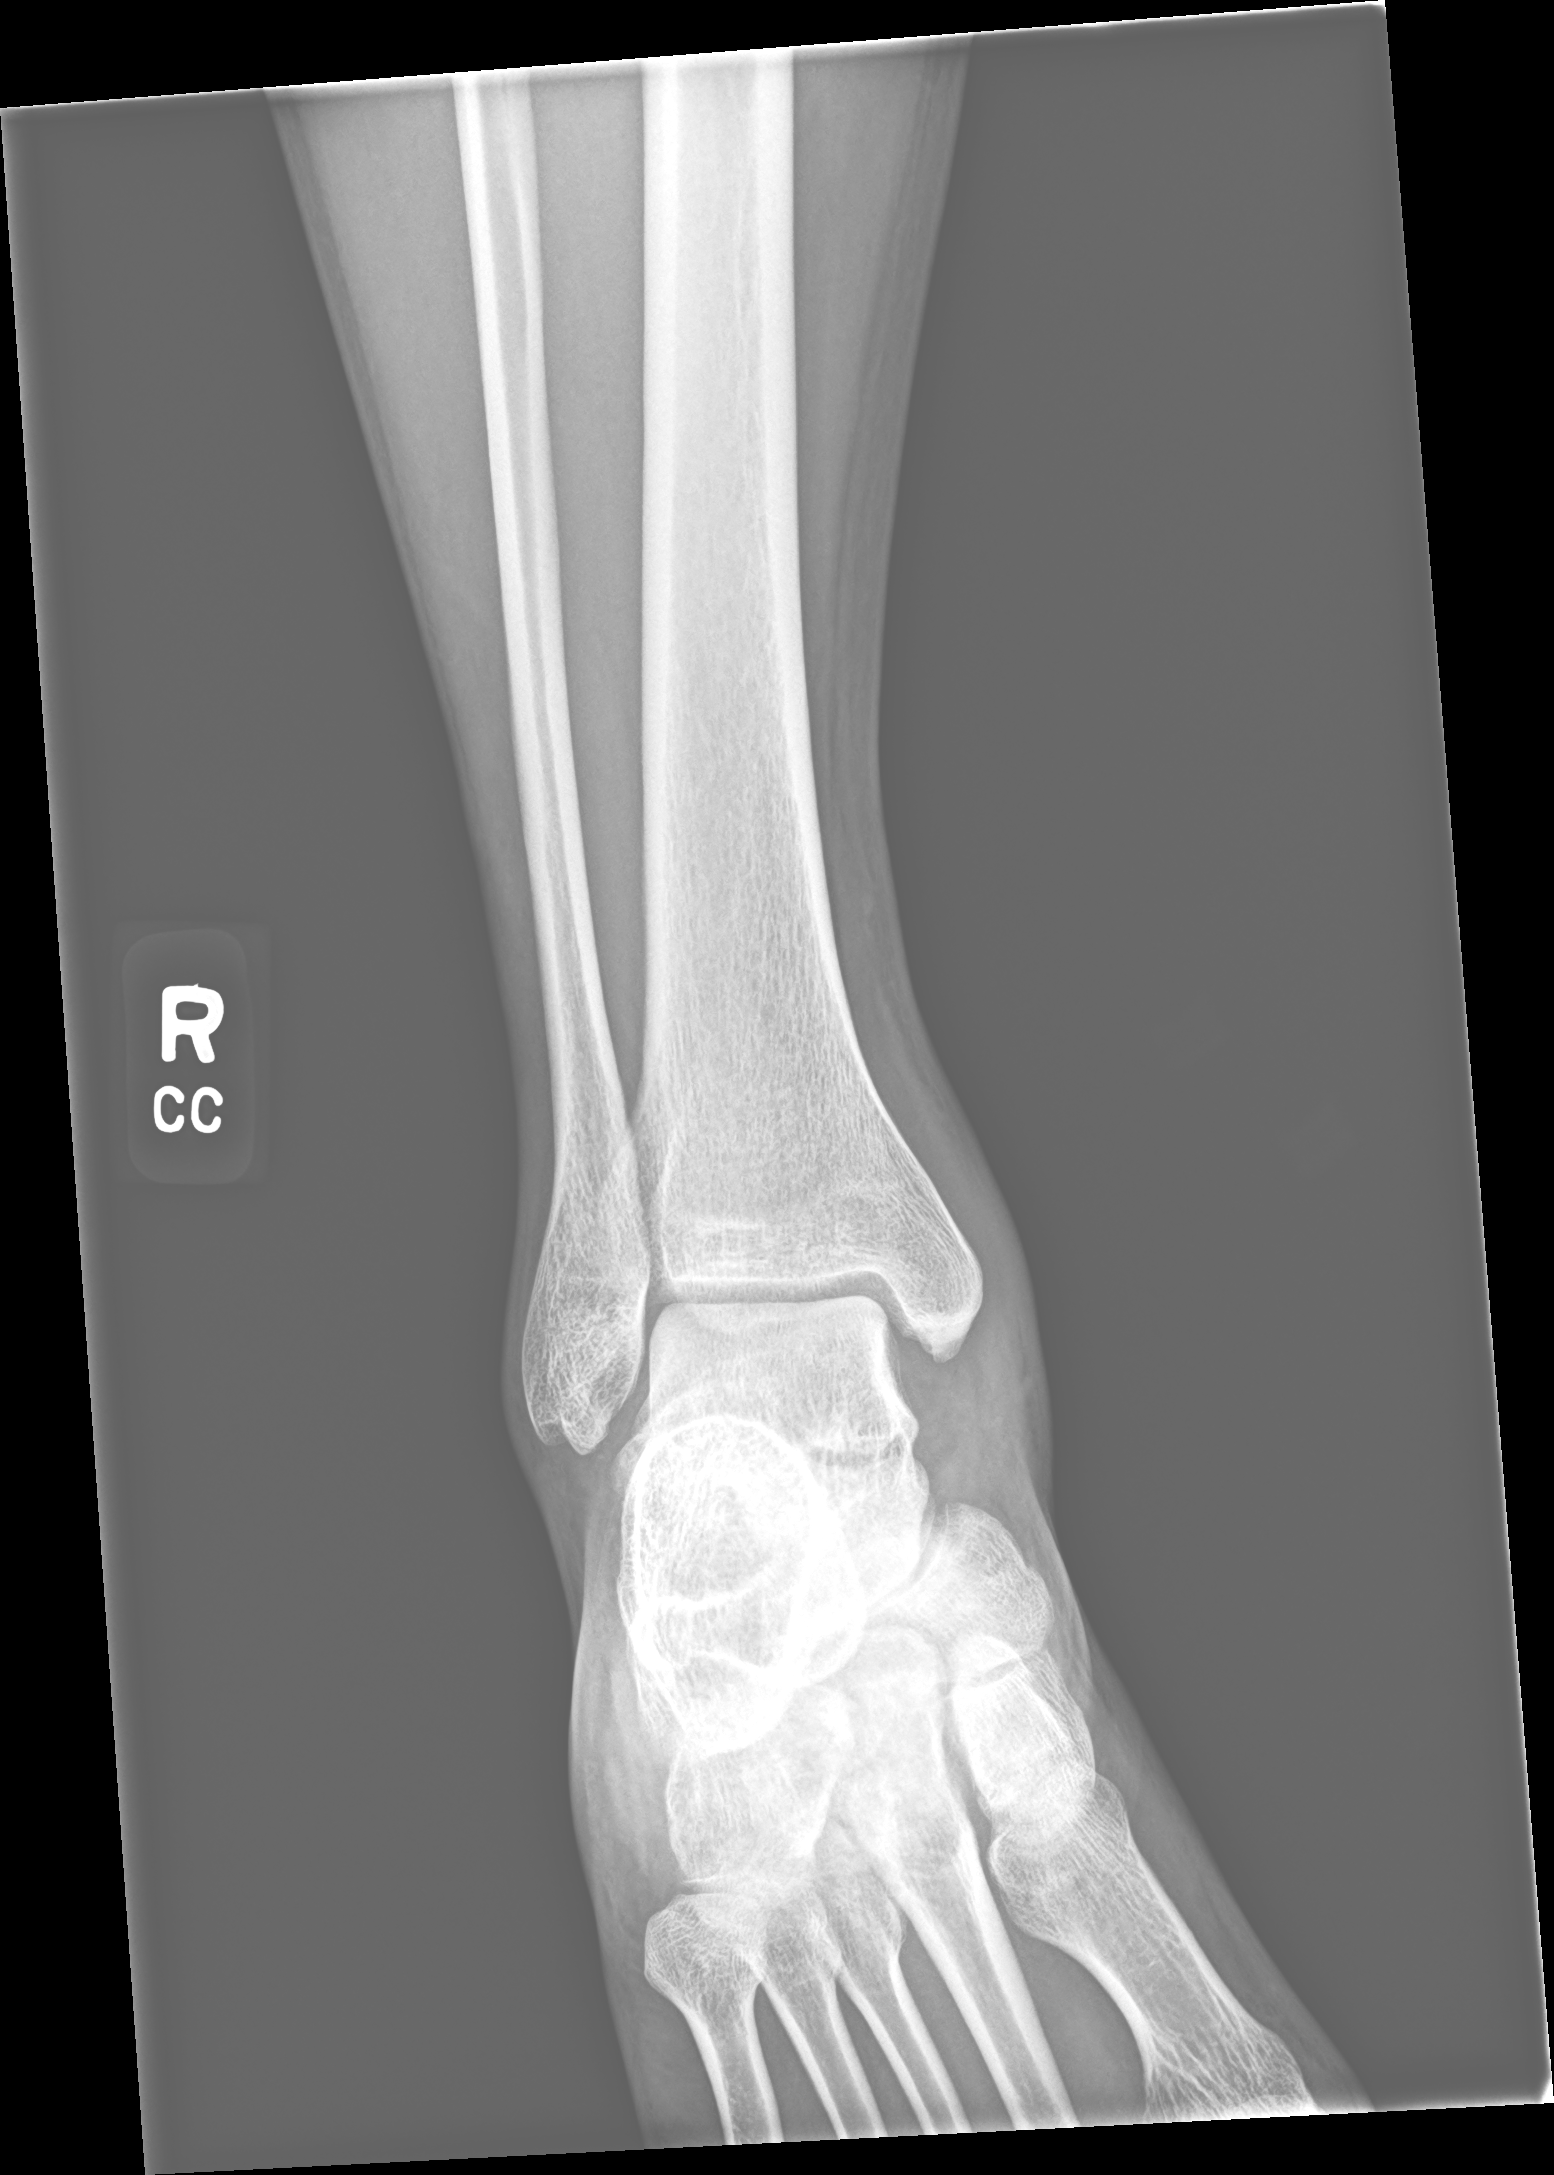

X 光补充信息

我同时把你补充的右踝 X 光一并纳入网页里。X 光能帮助看整体对位和有无明显大骨折, 但对距骨外侧突这类小的关节内骨折不如 CT 敏感,所以仍以 CT 为主。

我的补充看法

- X 光整体没有显示明显大块移位骨折或踝关节完全脱位。

- 踝穴总体对位尚可,和 CT 的整体印象一致。

- 但这并不能排除距骨外侧突或距下关节附近的小骨片损伤。

- 换句话说,X 光更像“没有大问题特别夸张地跳出来”,但 CT 仍提示外侧关节内骨性损伤更可疑。

X 光来源

- 检查日期:2026-04-02

- 模态:3 张 CR 原始片

- 用于补充整体对位判断,不替代 CT 细节分析